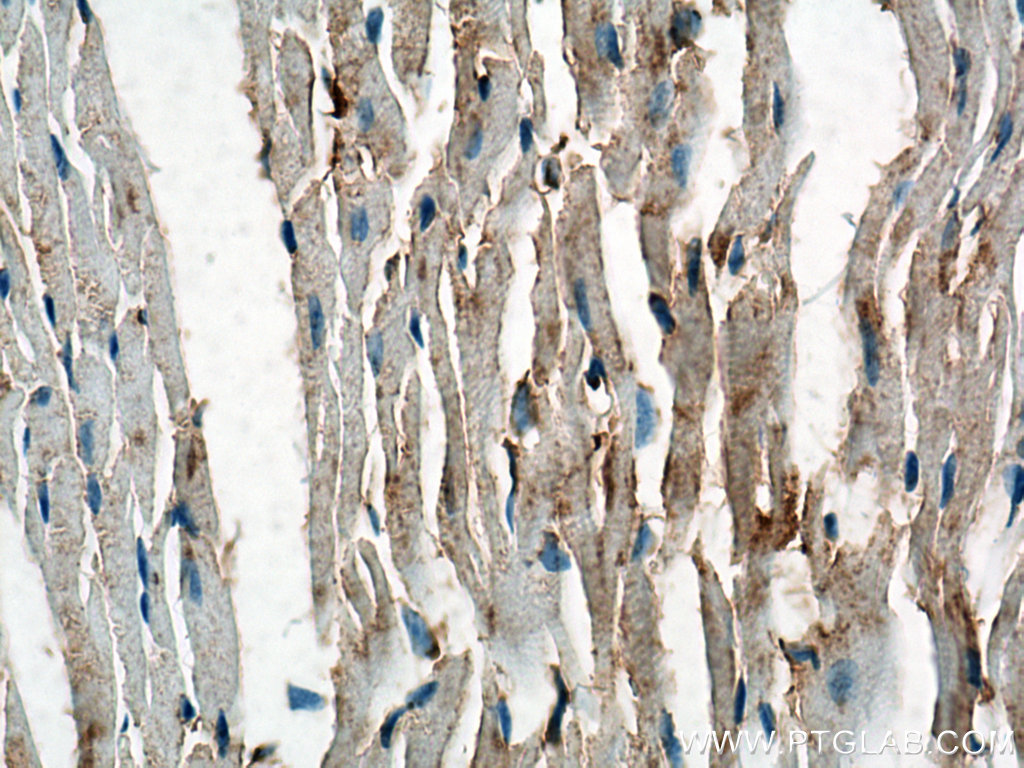

| Positive IHC detected in | mouse heart tissue Note: suggested antigen retrieval with TE buffer pH 9.0; (*) Alternatively, antigen retrieval may be performed with citrate buffer pH 6.0 |